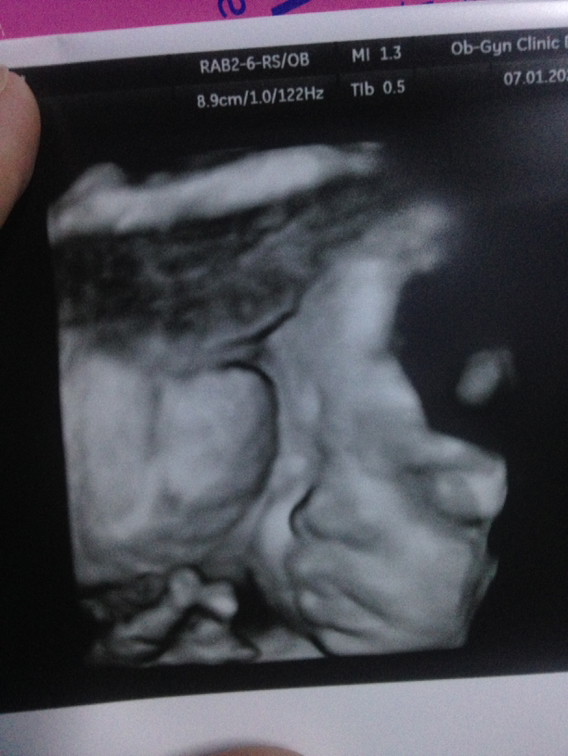

ค้าาา

ผู้ชายจ้า

ชายจ้า